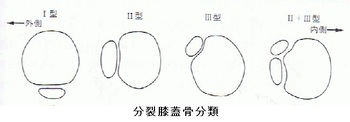

有痛性分裂膝蓋骨とは、膝蓋骨が2つまたはそれ以上に分裂していて、運動時や患部を押したり叩いたりして

痛みのある状態を言います。男子は、超音波観察から膝蓋骨の上外側に診られるⅢ型と認められました。

(下の分類図をご参照ください)